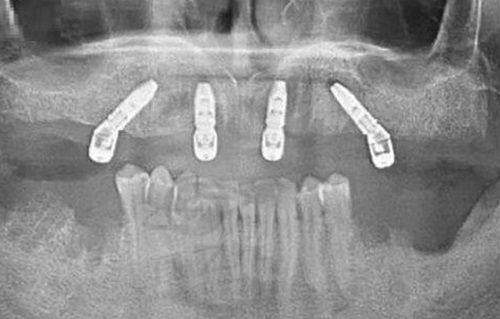

牙齿种植:无论是单颗牙齿缺失还是多颗牙齿缺失,都能在这里得到专精的种植治疗,帮助患者修复牙齿的咀嚼功能和美观。